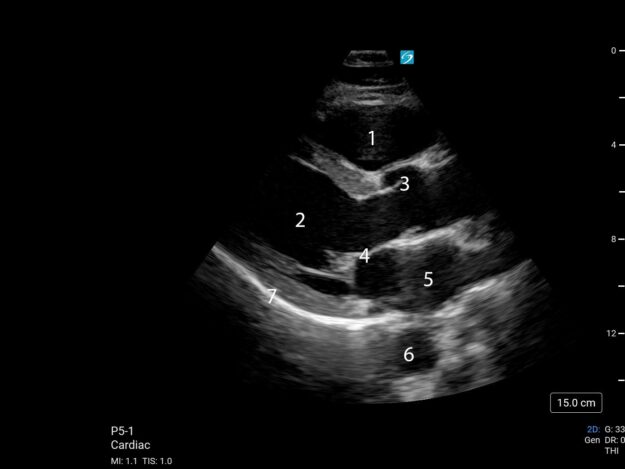

POCUS NEL CONTESTO PREOPERATORIO – CUORE Fabio Magarotto1, Federica Arturi1, Gabriele Melegari2 Università degli Studi di Modena e Reggio Emilia, Scuola di Specializzazione Anestesia e Rianimazione, Terapia Intensiva e del…